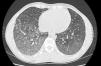

High-resolution chest-CT (HRCT) followed by CT angiogram were performed which helped to exclude pulmonary venous embolism and revealed extensive bilateral parenchymatous abnormalities with areas of “crazy-paving” pattern along with patchy ground-glass infiltrates with dependent distribution (Fig. 1).